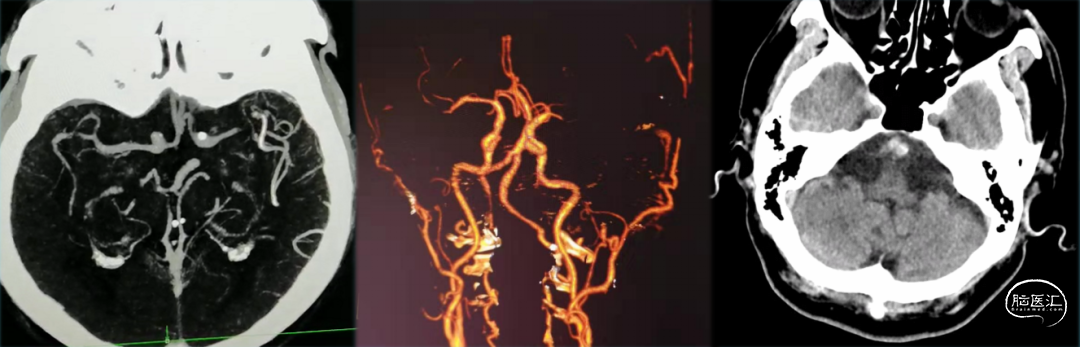

最后造影显示支架贴壁良好、支架内血运通畅、支架以远各级动脉分支显影良好。

对于颅内动脉慢性狭窄急性闭塞行逐级加奇SacSpeed® 2mm×9mm颅内球囊扩张可有效防止夹层形成,球扩成形良好后维持予欣维宁静脉抗板往往能维持责任病变的良好血运,可避免支架内急性血栓形成后闭塞的被动局面;对于部分出现管壁损伤的情况,使用开环支架修复损伤内膜、改善残余狭窄可能效果更好。

此病例中加奇SacSpeed® 2mm×9mm颅内球囊的优点非常明显:

a.加奇SacSpeed® 2mm×9mm颅内球囊充盈后显影性优良;

b.通过眼动脉弯等迂曲血管时柔顺性优良;

c.支架内后扩张操作过程中,加奇SacSpeed® 2mm×9mm颅内球囊进入支架、撤离支架均未见挂壁现象,安全性优良;

d.加奇SacSpeed® 2mm×9mm颅内球囊完全充盈后成形效果优良。